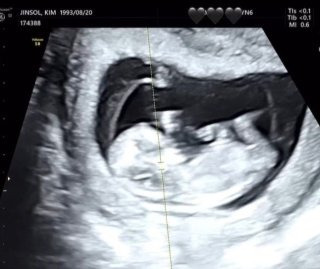

트루디 임신 출산

트루디는 결혼 후 임신 소식을 전하며 큰 축하를 받았다. 방송과 SNS를 통해 임신 사실을 공개했고, ‘골때녀’ 활동 중에도 팀원들에게 직접 알리며 감동을 전했다. 이후 건강한 출산을 위해 방송 활동을 잠시 중단했다.

2025년 11월 아들을 출산하며 엄마가 됐다. 출산 이후 SNS를 통해 아기의 모습을 공개하며 팬들과 기쁨을 나눴다. 육아와 함께 새로운 인생의 변화를 맞이한 모습이 많은 관심을 받고 있다. 임신 준비에 어려움이 있었지만 결국 임신과 출산에 성공하면서 행복한 가족에 마침표를 찍었다.